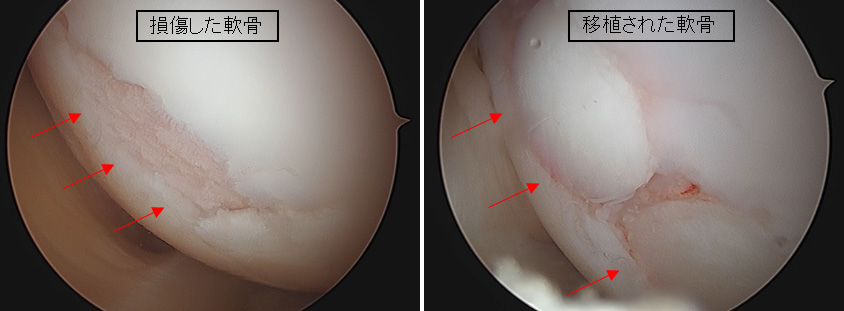

③ 自家骨軟骨柱移植術(じかこつなんこつちゅういしょくじゅつ)

モザイクプラスティなどとも呼ばれています。自身の機能破綻を生じしにくい部分から軟骨と軟骨下骨を円柱状に採取し、それを軟骨欠損部へ移植させることで損傷部位の軟骨修復を図る方法になります。この方法は比較的大きな軟骨損傷にも適用できるとされていますが、自身の正常軟骨を使用するため、採取できる軟骨の量に限界があります。(図2. 3. 4)

【図4 関節鏡でみえる離断性骨軟骨炎 その2

(左:手術前の損傷した軟骨、右:骨軟骨柱移植術後の軟骨)】